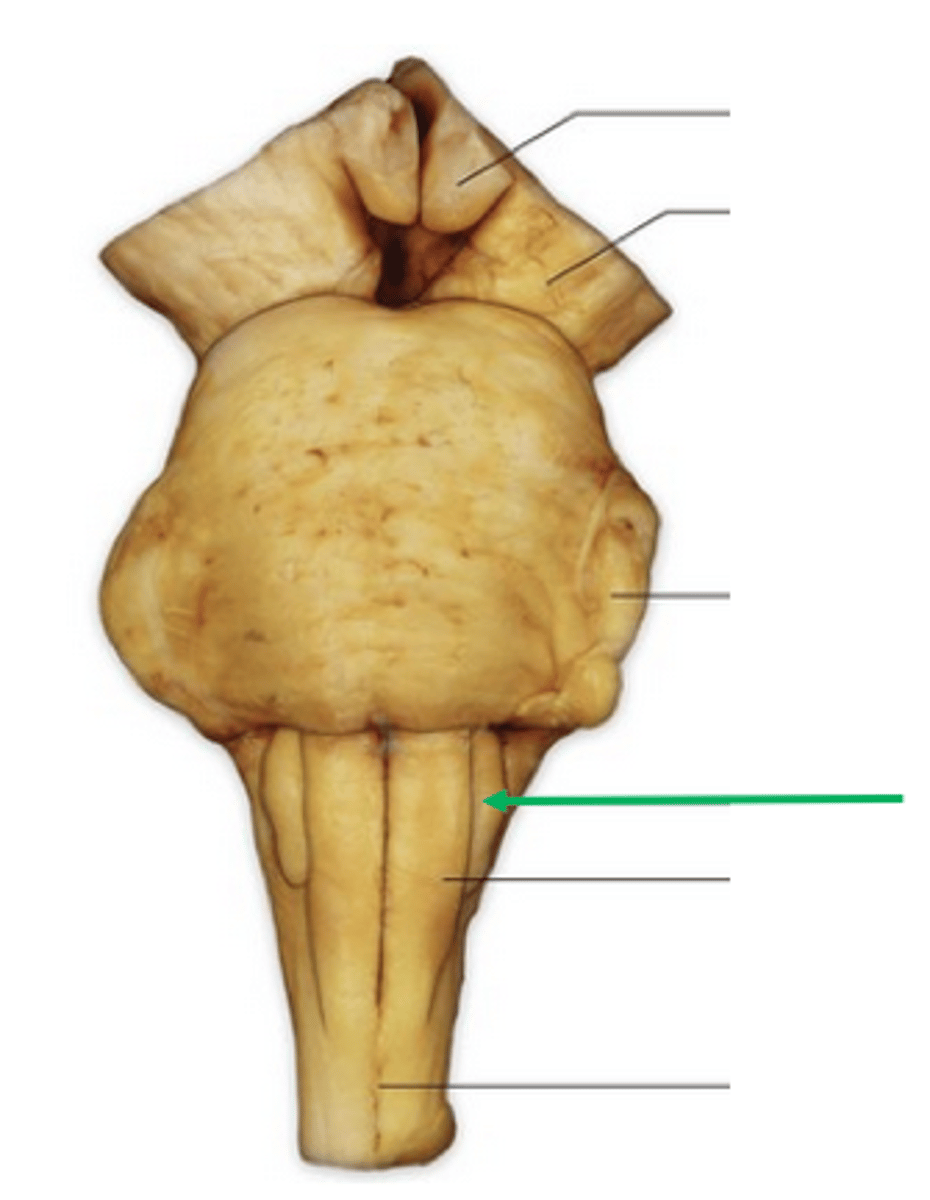

name the groove

pontomedullary junction

general portion of the medulla

open medulla

general portion of the medulla

closed medulla

pyramids

ventral median fissure

pyramidal decussation

C

inferior cerebellar peduncles

cuneate tubercle

gracilis tubercle

cuneatus tract

gracilis tract

obex